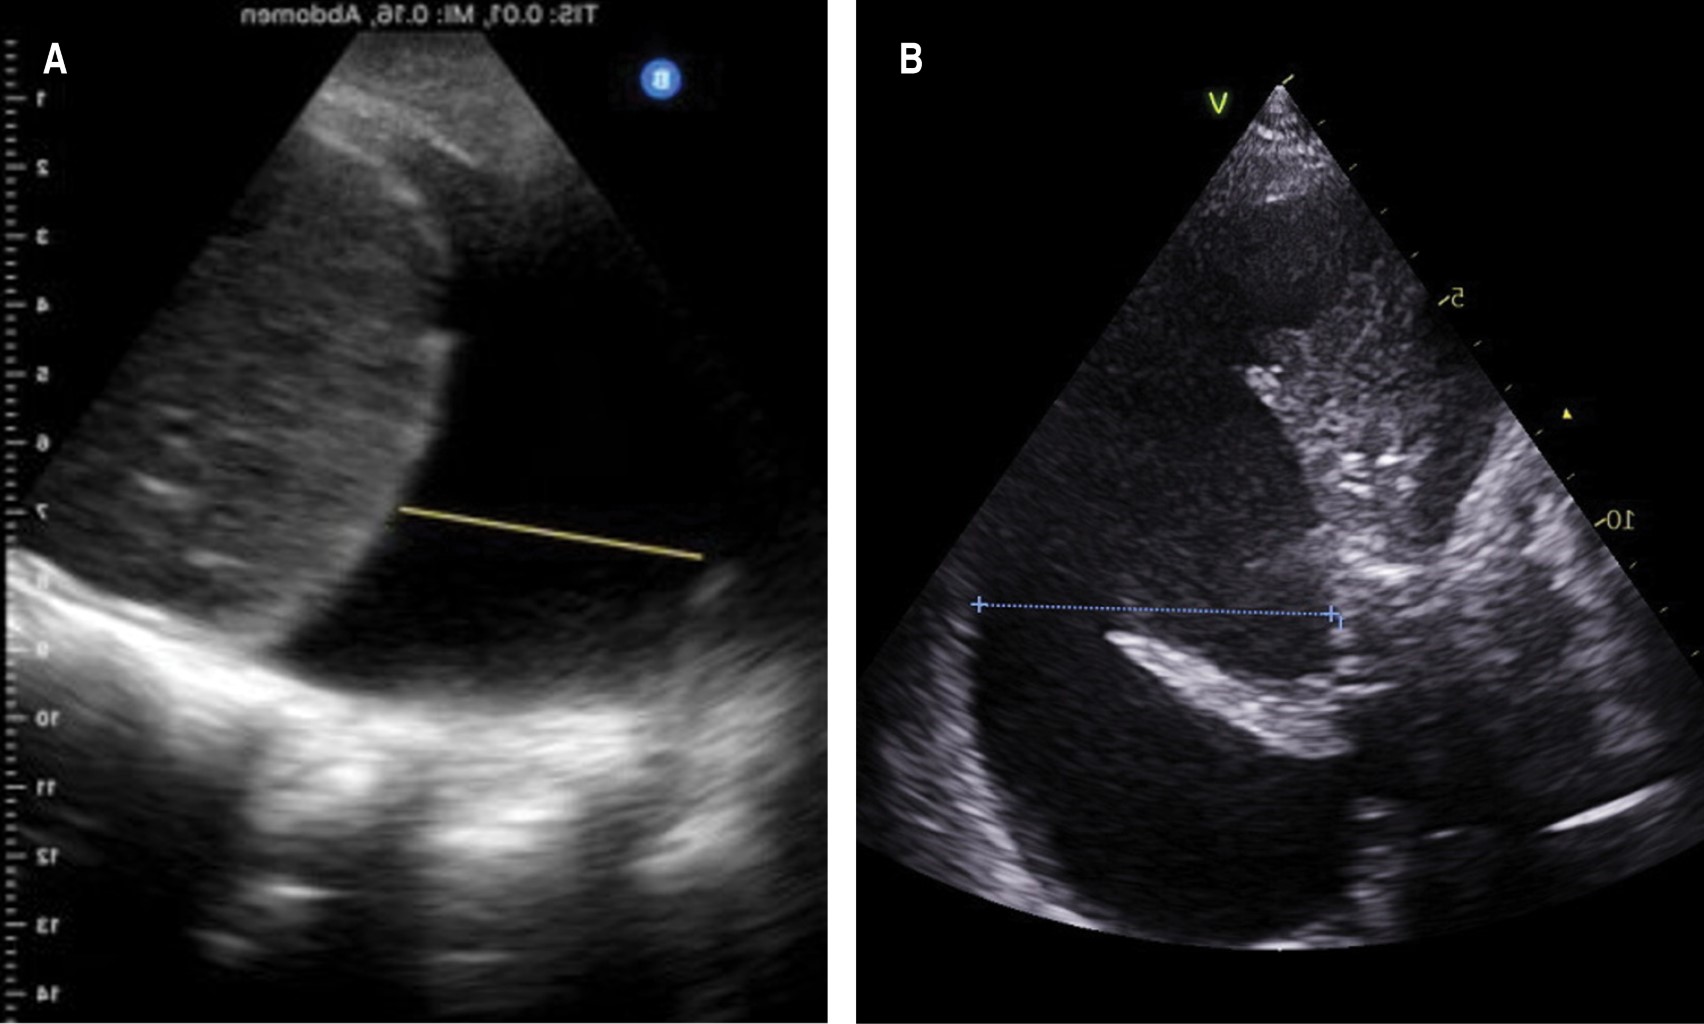

Utilidad de la fórmula de Balik para la cuantificación del derrame pleural por ultrasonido en el posoperatorio de cirugía cardiaca

Cruz-Rodríguez, Camelia1; García-Cruz, Edgar1; Gopar-Nieto, Rodrigo1; Lazcano-Díaz, Emmanuel1; Ordaz-Figueroa, Diana Lizbeth1; Elizalde-Silva, José Luis1; Rojas-Velasco, Gustavo1; Manzur-Sandoval, Daniel1